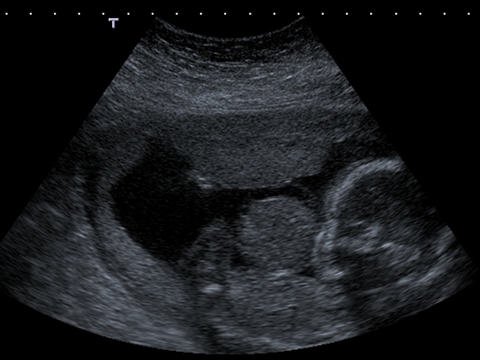

A long axis scan through the fetus shows the herniated liver coming from the anterior abdominal wall of the fetus. The fetal limbs, abdomen and head can also be seen.